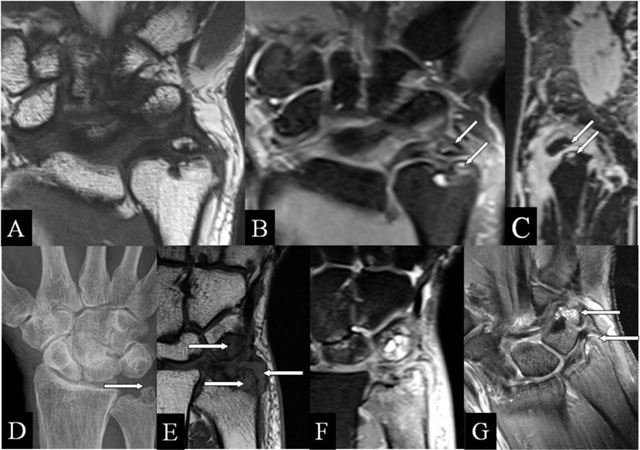

Figure 3

Ulnar (intra)styloid and stylotriquetral abutment. (A, E) Coronal SE T1-WI; (B, F) Coronal SE PD-WI FS; (C) Sagittal 3D-GRE; (D) PA plain radiograph; and (G) Coronal SE T1-WI FS with gadolinium. (A–C) Neoarticulation in the center of the ulnar styloid process, surrounding marrow oedema, (B) and juxta-articular cysts (arrows) (B, C). (D–F) Stylotriquetral abutment with flattening of the tip of the styloid process (D), bone marrow oedema and synovitis (E, F), and contrast enhancement of the marrow oedema and the synovitis (G).

Ulnar (intra)styloid abutment

Styloid process fractures may fail to heal, resulting into fragmentation and collision during ulnar deviation. MRI highlights neo-articulation and BMO (Figure 3A–C). The triangular fibrocartilage complex (TFCC) ulnar insertion (fovea and tip) in relation to these fragments is depicted (Figure 3B). Basal fractures may lead to DRUJ instability [910]. Ultrasound or MRI performed in pronation and supination may confirm a dynamic extensor carpi ulnaris tendon dislocation (empty sulcus sign).

Stylo-triquetral abutment

Due to styloid process length increase, impaction with the triquetral bone may appear (Figure 3D–G). As in the classical abutment, the Garcia-Elias index [11] may indicate the risk of SAS development. Surrounding synovitis is frequent (prestyloidal synovitis).